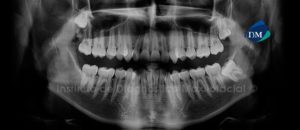

Paciente masculino de 15 años de edad que es referido para la evaluación de los terceros molares. La radiografía panorámica nos muestra la presencia de